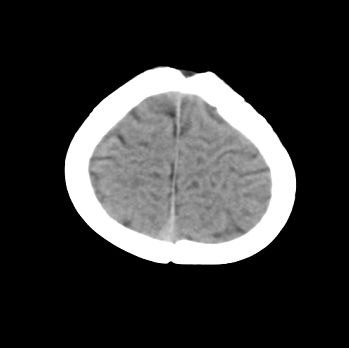

以下是引用fgp198在2008-6-9 12:16:00的发言:[br]病灶周围见脑组织包绕,上部可见等或稍高密度壁环绕,壁且见小点钙化-----考虑皮样囊肿或表皮样囊肿可能